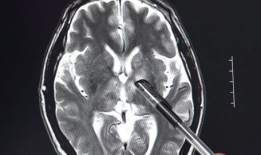

脑膜刺激征检查视频,直观解析临床诊断技巧

你有没有想过,去医院看病的时候,医生有时候会给你来点“特殊待遇”?比如说,给你做个脑膜刺激征检查。这听起来是不是有点陌生?别急,...